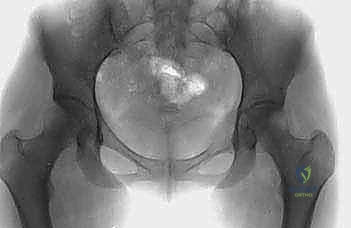

عندما يغزو السرطان منطقة الحوض، فإنه لا يكتفي بتدمير البنية العظمية الصلبة فحسب، بل يتسبب في سلسلة من المضاعفات المنهكة. يشمل ذلك الآلام الميكانيكية والبيولوجية الشديدة التي لا تستجيب للمسكنات التقليدية، وفقدان القدرة على المشي أو تحمل الوزن، فضلاً عن الخطر الداهم بحدوث "الكسور المرضية" – وهي كسور تحدث نتيجة إجهاد بسيط على عظم نخرة الورم وأضعفه. ونظراً لاتساع تجويف الحوض، ومرونة العضلات والأعضاء المحيطة به، قد تنمو هذه الأورام لأحجام كبيرة (أورام عملاقة) قبل أن تظهر أعراضها بوضوح، مما يجعل التدخل الطبي المتأخر أكثر تعقيداً.

- أورام الحُق (Acetabulum): هذه هي الحالات الأكثر تعقيداً وإلحاحاً. تدمير سقف الحُق يعني أن رأس عظم الفخذ سيندفع داخل تجويف الحوض عند محاولة المريض الوقوف، مما يسبب ألماً يفوق الوصف وقصراً في الطرف السفلي. تتطلب هذه الحالات خبرة جراحية استثنائية لإعادة بناء التجويف باستخدام الإسمنت العظمي، الدعامات المعدنية، أو المفاصل الصناعية المخصصة (Custom-made Endoprostheses).

تُستخدم هذه التقنية المتقدمة عندما يكون الورم قد دمر منطقة "الحُق" (سقف مفصل الورك).

* يقوم الدكتور هطيف بإدخال دبابيس معدنية ملولبة قوية (Threaded Pins) عبر العظم الحرقفي السليم لتصل إلى منطقة الحُق.

* يتم تشكيل كتلة من الإسمنت العظمي حول هذه الدبابيس لإنشاء "سقف صناعي" جديد ومتين لمفصل الورك.

* بعد ذلك، يتم تركيب مفصل ورك صناعي كامل (Total Hip Arthroplasty) يرتكز على هذا السقف الإسمنتي القوي، مما يسمح للمريض بالمشي مجدداً دون ألم.